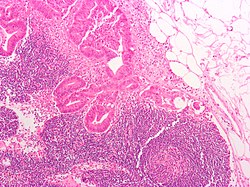

| Toxoplasmosis | large follicles; epithelioid cells perifollicular & intrafollicular | reactive GCs, monocytoid cell clusters, epithelioid cells | IHC for toxoplasma | NSRFH, HIV/AIDS, Hodgkin's lymphoma | File:Toxoplasmosis lymphadenopathy - low mag.jpg TL - low mag. |

Toxoplasma lymphadenitis

General

- Caused by protozoan Toxoplasma gondii.

Microscopic

Features:[7]

- Reactive germinal centers (pale areas - larger than usual).

- Often poorly demarcated - due to loose epithelioid cell clusters at germinal center edge - key feature.

- Epithelioid cells - perifollicular & intrafollicular.

- Loose aggregates of histiocytes (do not form round granulomas):

- Abundant pale cytoplasm.

- Monocytoid cells (monocyte-like cells) - in cortex & paracortex.

- Large cells in islands/sheets key feature with:

- Abundant pale cytoplasm - important.

- Well-defined cell border - important.

- Singular nucleus.